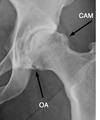

This is interesting! And thought provoking. Yes, you do have some mild arthritis but that's been slowly developing over the years. What is unusual is the very large CAM deformity arrowed; you have a condition called femoro acetabular impingement syndrome. It causes the frozen hip that your PT describes, and isn't new either; you may not have realised it but you've had a stiff hip for years.

Yes, there is some distorsion of the pelvis; was this radiograph taken standing? If so you have a short leg and, combined with the CAM deformity is why it's turning arthritic. You should be wearing an orthotic in your shoe, thicker on the right.